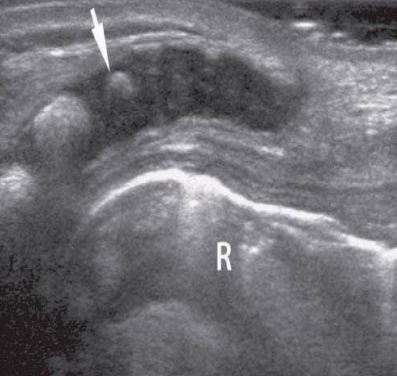

white arrow

end of thecal sac (about s2)

partially calcified coccyx

r

rectum filled with air

c

hypoechoic spinal cord

arrows

echogenic nerve roots of cauda equina

arrowheads

echogenic dura

*

echogenic vertebral arches

p

spinous process